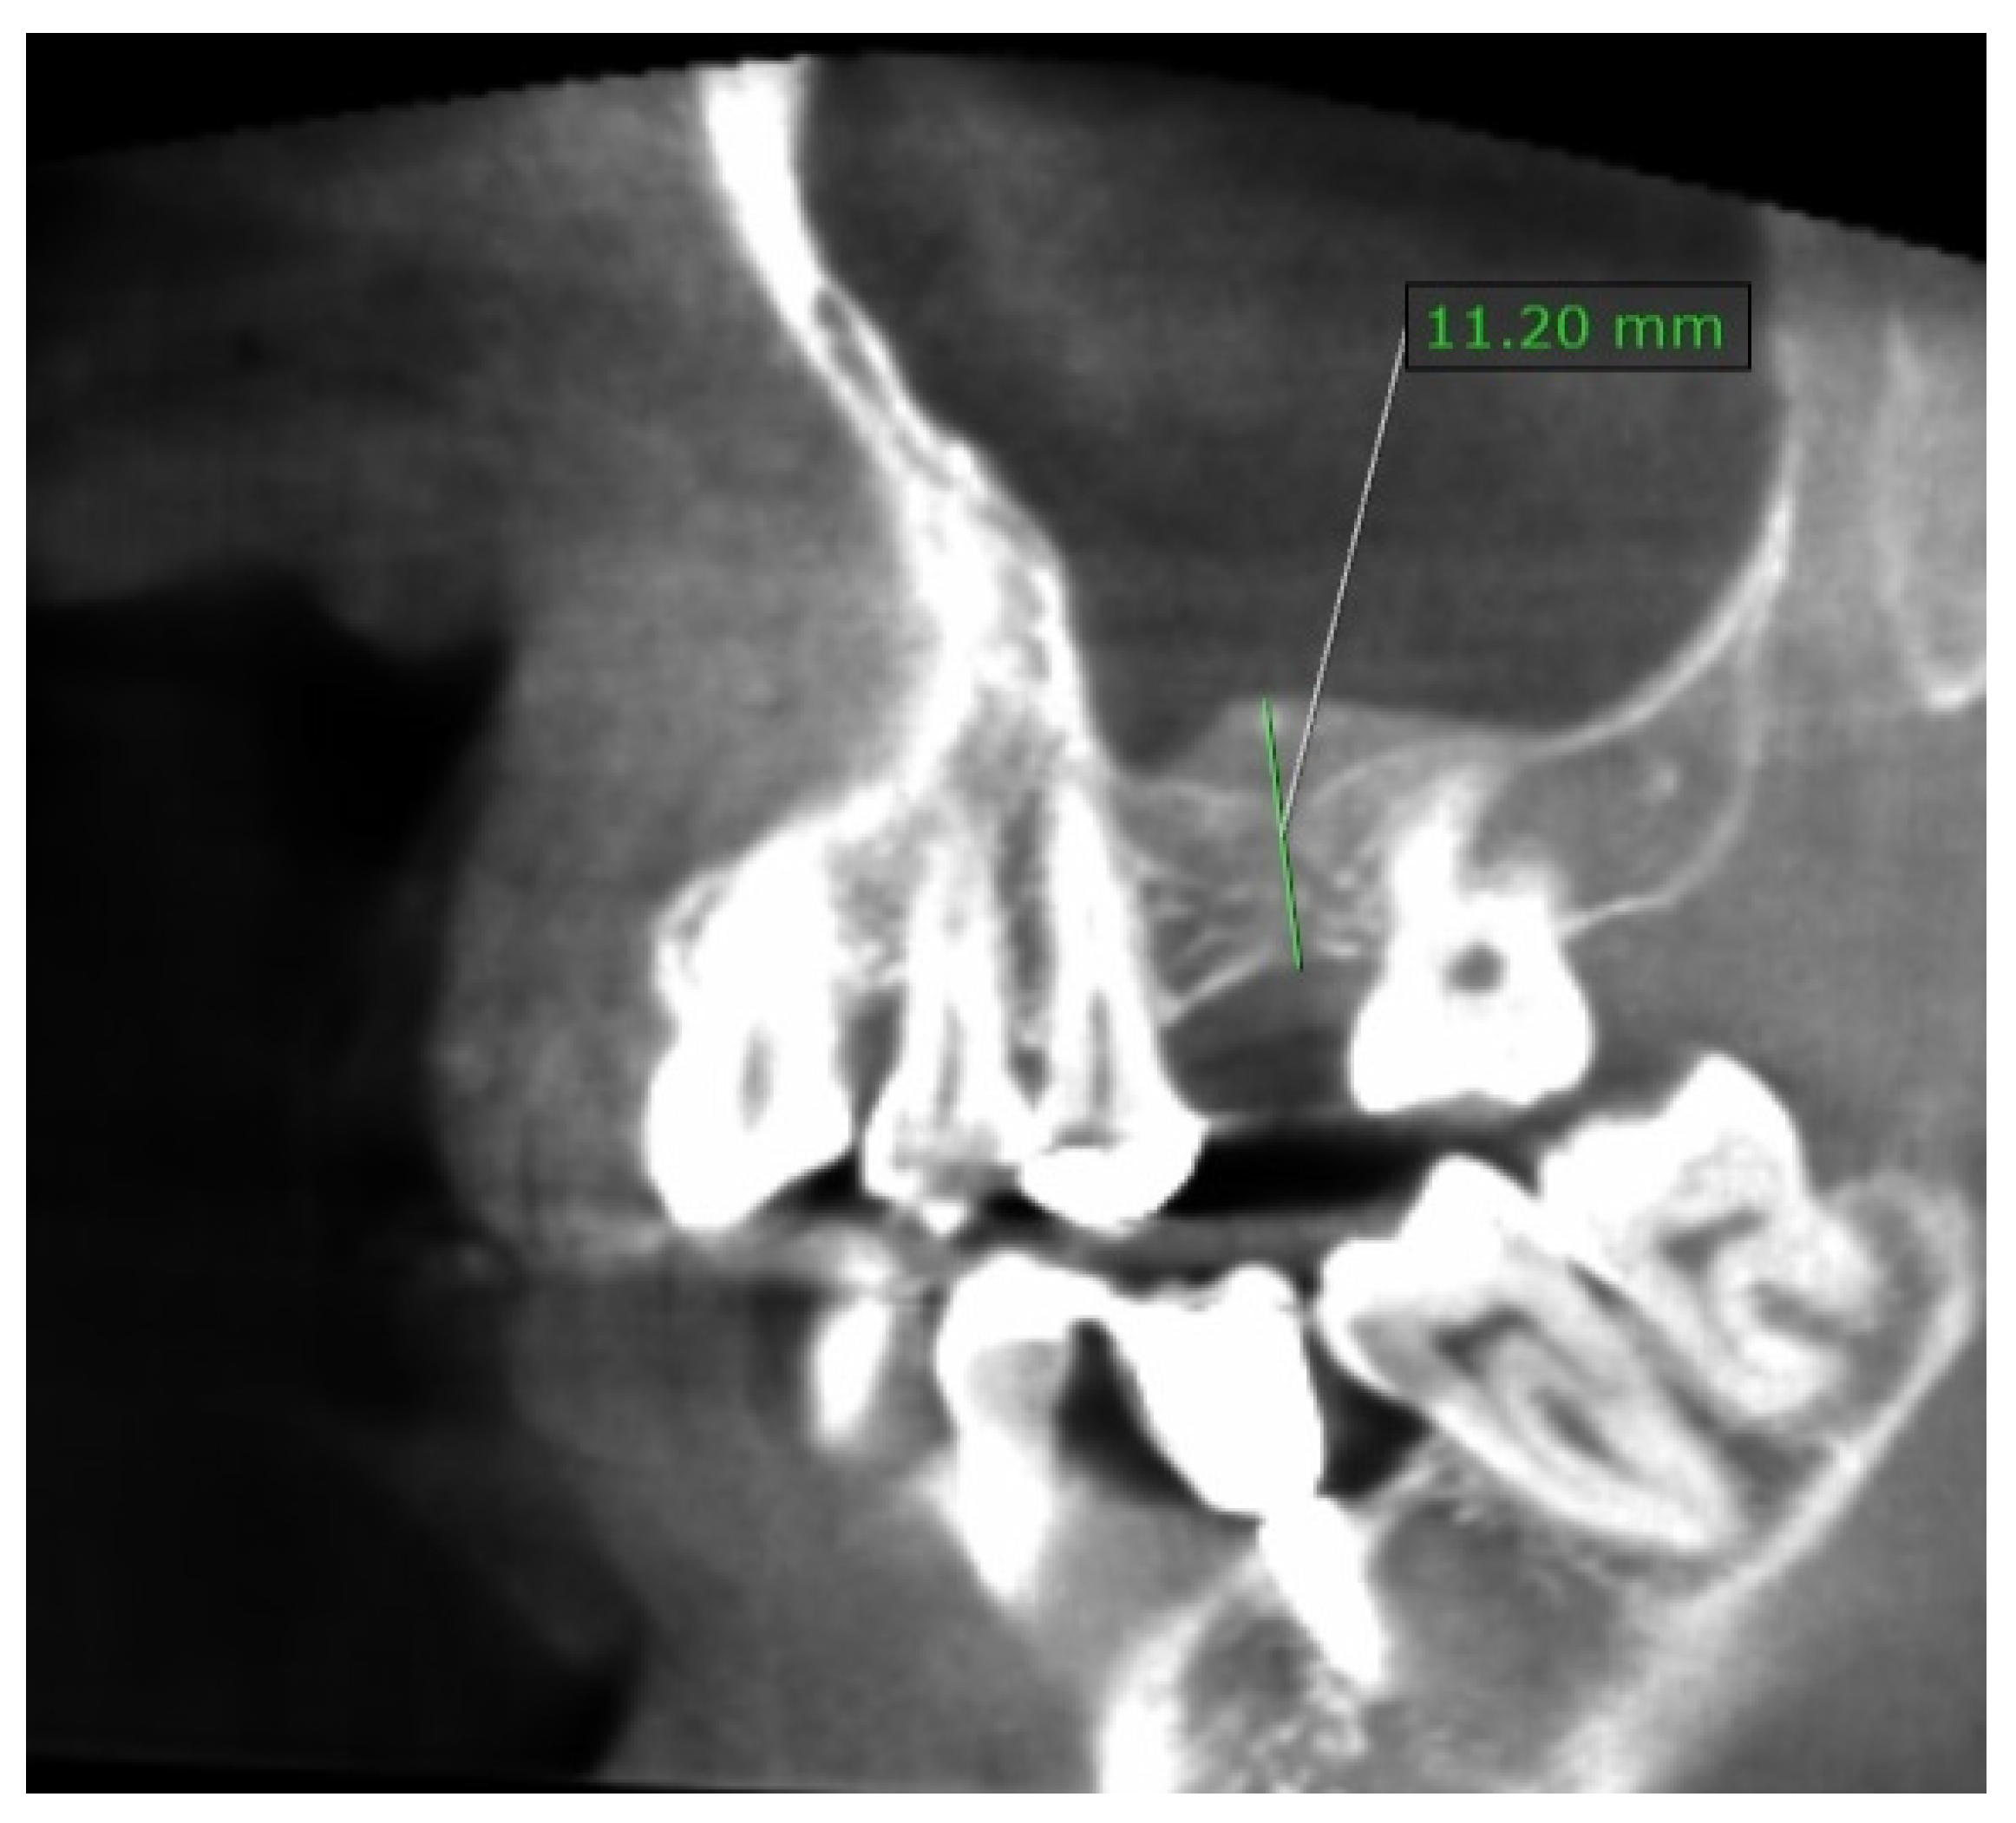

Case Presented with Histomorphologic Evaluation